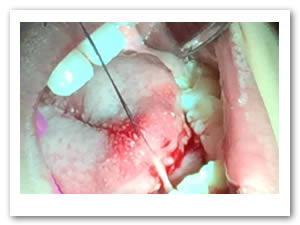

• Se pasa una sutura sin anudar en la punta de la lengua para traccionar la misma y facilitar las maniobras quirúrgicas. Posteriormente se utilizan dos pinzas de mosco, una curva y una recta pinzando el frenillo en su borde superior e inferior para limitar sus bordes. Figuras 3 y 4.

Figura 3. Sutura sin anudar en punta de la lengua

Figura 4. Pinzado del frenillo